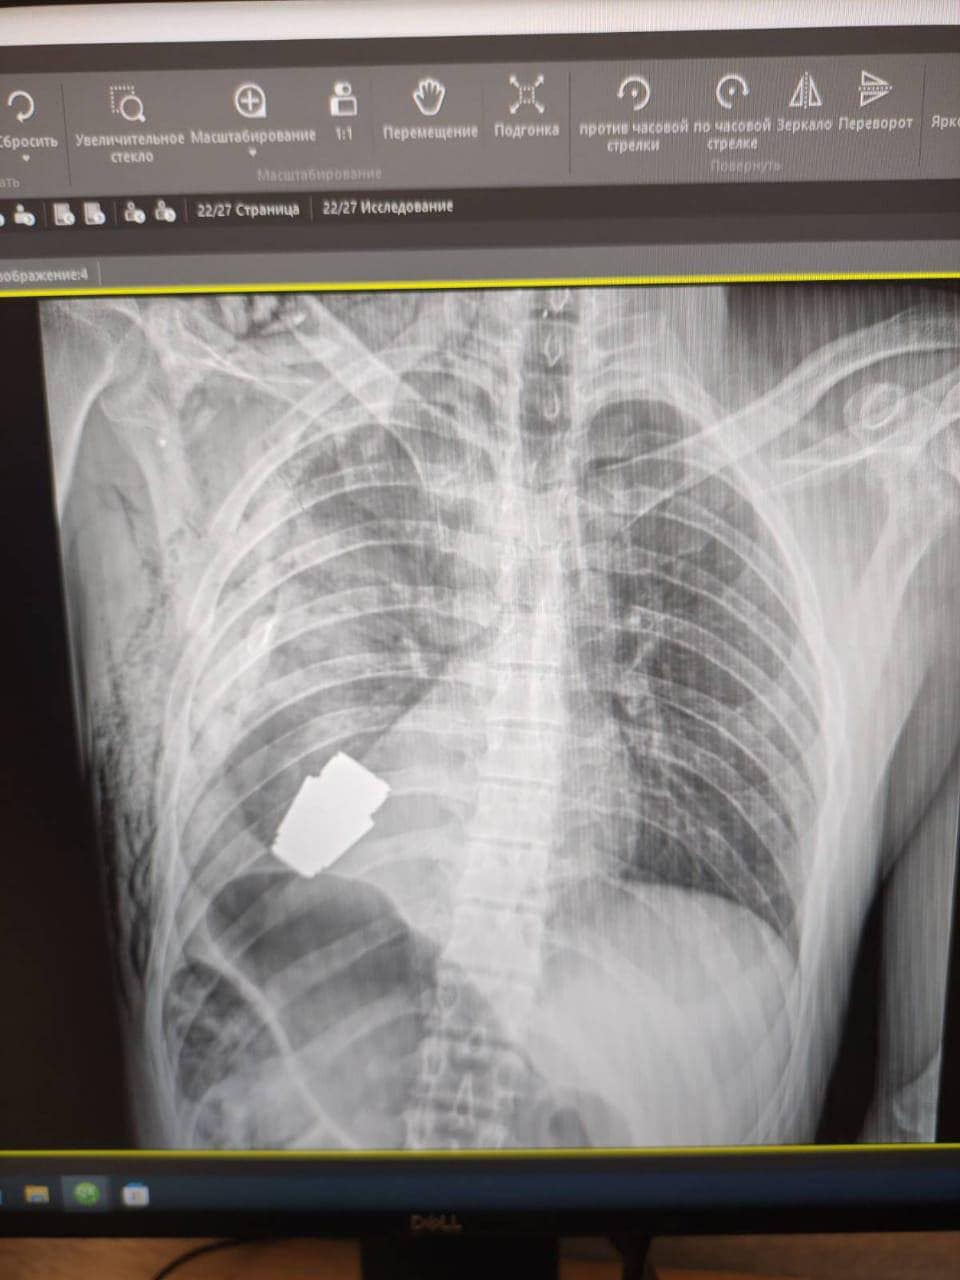

L’esplosivo era rimasto intatto nel torace del soldato, così come mostrano le immagini postate sui social dall’alto funzionario di Kiev: “I medici militari hanno condotto un’operazione per rimuovere una granata VOG, che non si è rotta, dal corpo del soldato”, ha spiegato la Maliar.

La vice ministra ha postato l’immagine di una radiografia in cui si vede l’ordigno all’interno del corpo del soldato e una foto di un chirurgo che osserva la granata dopo l’intervento.

La parte inesplosa della granata si trovava sotto il cuore del militare ferito, ha precisato Gerashchenko.